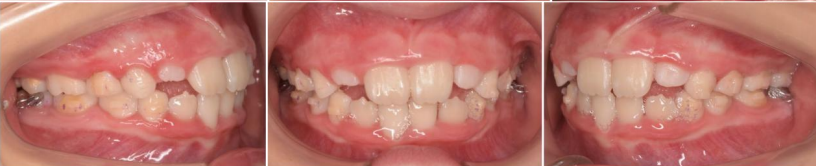

这位11岁孩子主诉嘴凸、下巴后缩,家长带孩子来做矫正,也是怕来晚了,孩子嘴凸、下巴后缩会越来越严重。

考虑到孩子还在生长发育阶段,还有一定的生长潜力,综合考虑孩子的牙齿、面型情况之后,制定不拔牙矫正方案,使用隐形牙套。

关键一点是通过推磨牙向远中+扩弓来获得间隙,解决前后牙距离大、内收排齐牙齿、把上下牙角度调直,调整咬合平面角度,创造下巴前伸的条件。